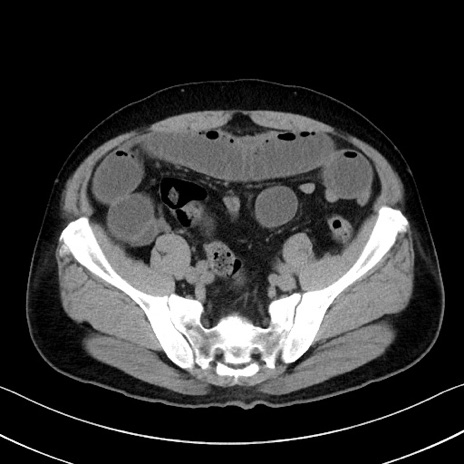

症例35(横断像)

【症例】70歳代 男性

【主訴】腹部膨満、嘔吐

【現病歴】昨日より腹部膨満感出現。本日増悪し、仙痛出現。嘔吐あり、受診。

【既往歴】糖尿病、胆摘後

【身体所見】BP 149/80mmHg、HR 74/min、BT 35.9℃、腹部:膨満、軟、圧痛なし。腸雑音減弱あり。上腹部正中切開瘢痕あり。

【データ】WBC 13500、CRP 1.72